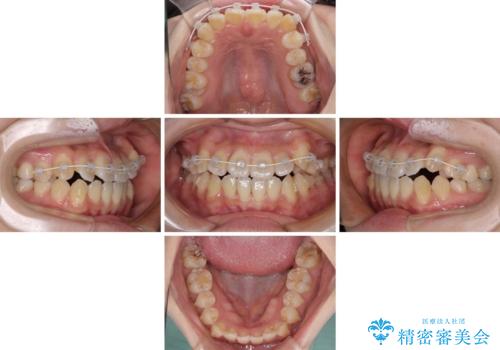

【モニター】前歯のデコボコを改善 ワイヤー矯正を併用したインビザライン矯正

- 八重歯や前歯の捻転とクロスバイトが気になり、インビザラインによる矯正治療を希望して来院された患者様です。

上顎側切歯(上の真ん中から2番目の歯)が舌側転位している場合、無理して動かそうとすると歯髄壊死を起こすリスクが高い印象があります。

インビザライン単体でも治療は可能ですが、安全策としてインビザラインで歯列を移動する前に上顎前歯をワイヤー矯正で整え、その後上下歯列をインビザラインにて矯正治療を行うこととしました。

舌側転位している側切歯特有の、切縁の位置が不揃いであったり、根元が内側に引っ込んだ状態であったりという、インビザライン独特の仕上がりになることなく、きれいに整った歯列とすることができました。